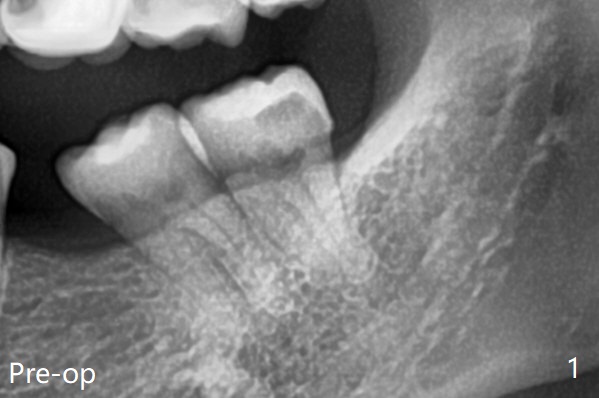

粘性骨粉植骨(图二:*)。术后一两个月(伤口愈合,18号牙牙冠远中面充分暴露)后,准备口扫做无形局部矫正(Clear Aligner),竖直18号牙。然后再口扫制作19号牙种植导板。